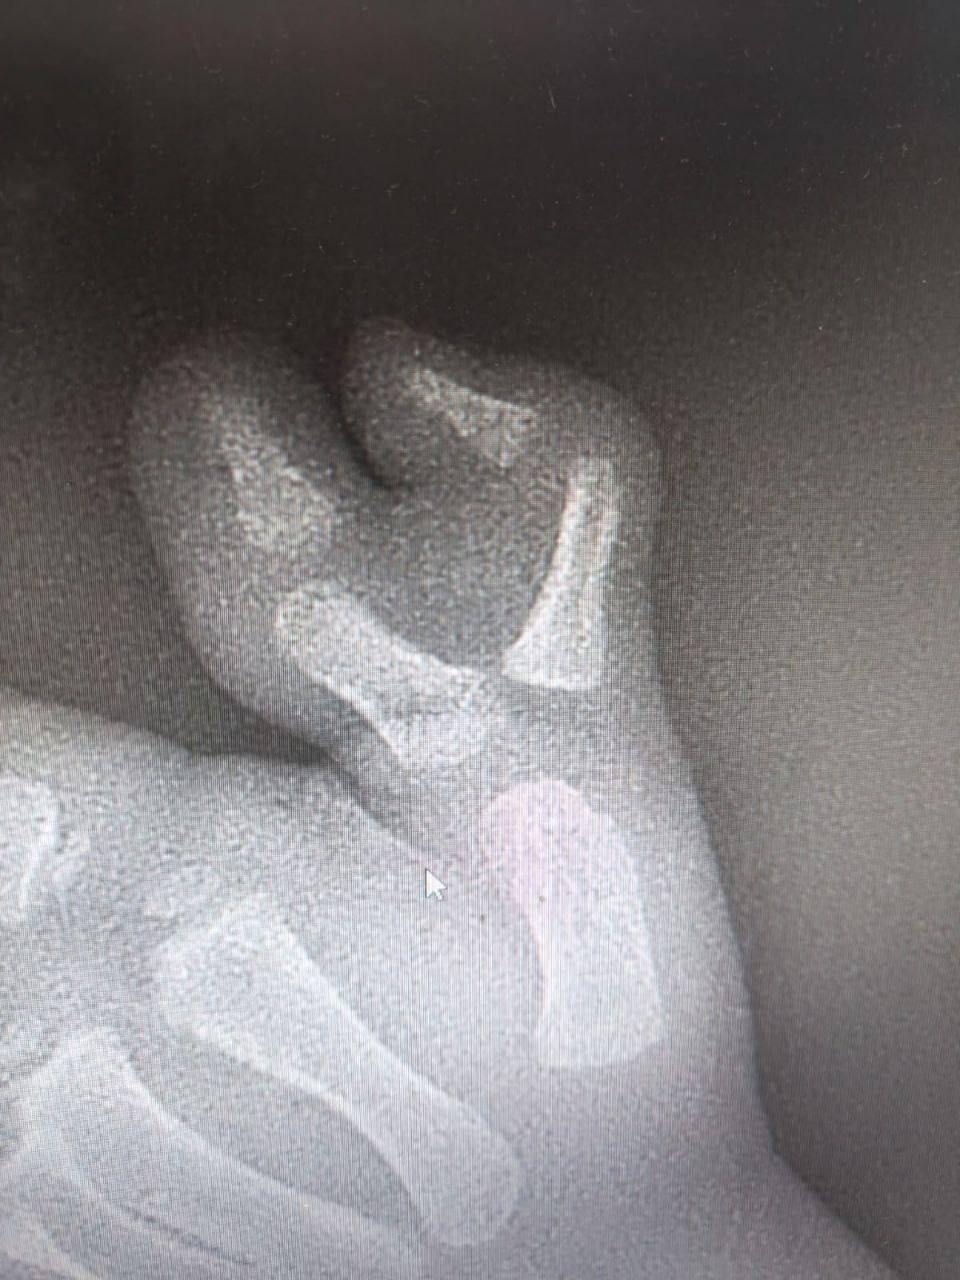

Врачи Московской областной детской клинической травматолого-ортопедической больницы помогли трехлетнему ребенку с редкой врожденной аномалией — на одной руке у него рос шестой палец. Это мешало малышу не только физически, но и вызывало психологический дискомфорт.

Хирурги больницы после тщательного обследования провели реконструктивную операцию: они аккуратно удалили лишний палец и сформировали нормальное строение кисти. Функции руки малыша при этом были полностью сохранены.

После операции мальчика выписали домой, вскоре ему планово удалят металлоконструкции, после чего он сможет жить без воспоминаний о своей врожденной особенности.